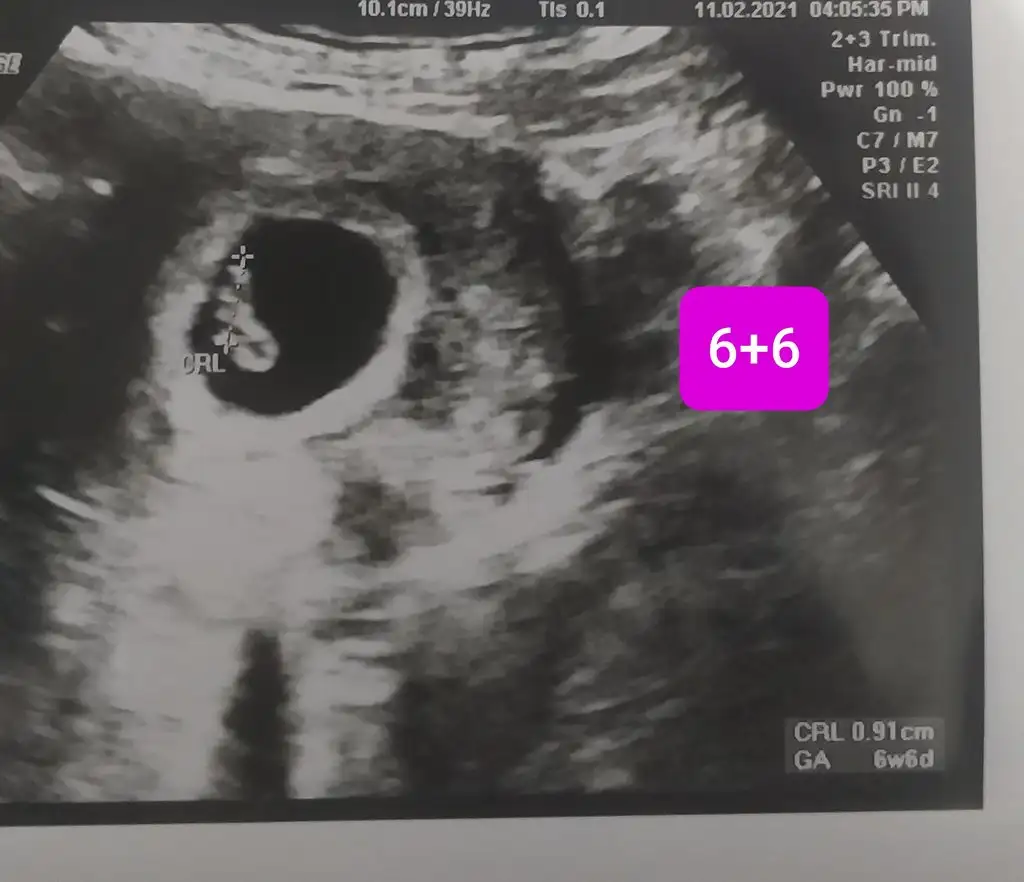

6+6 haftalık karından ultrason bana da yorum yapabilir misiniz?

• 20210211_234714.webp

20210211_234714.webp

25,1 KB · Görüntüleme: 121